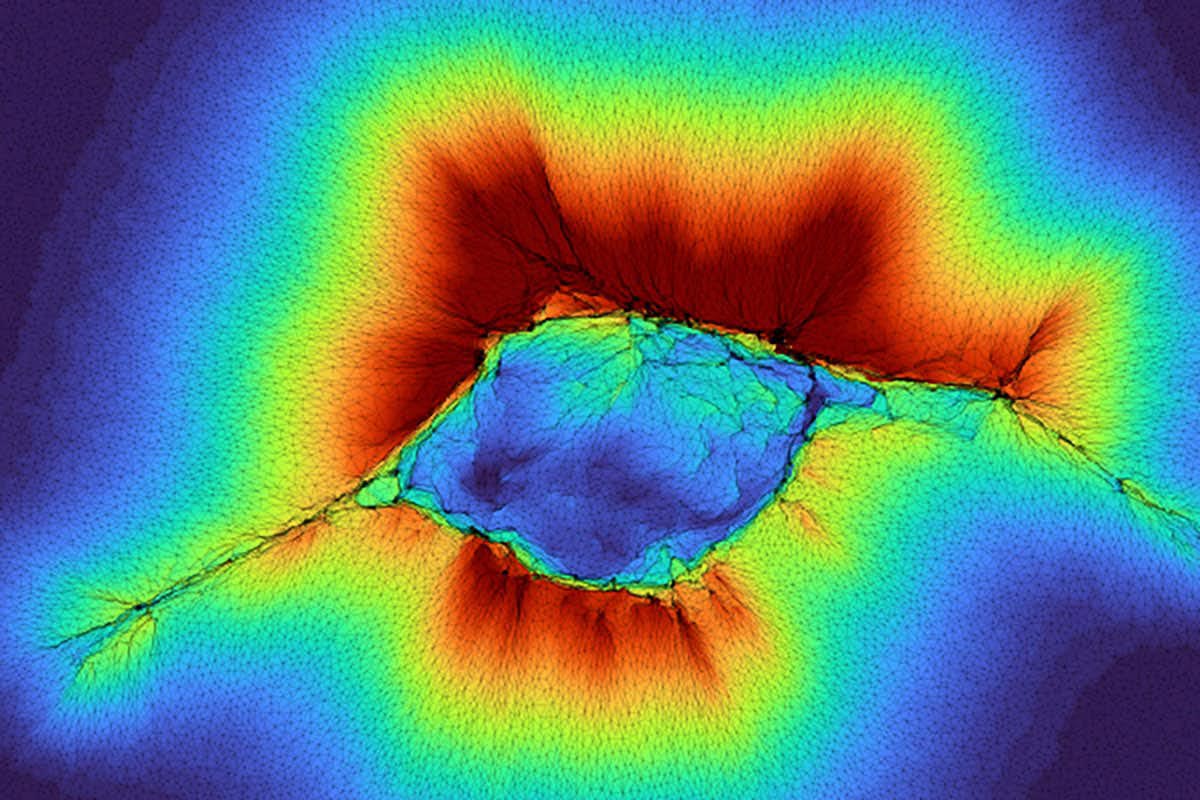

У цій моделі клітинні кластери можуть «відчувати» те, що знаходиться далі за межами їхнього оточення в людському тілі, діючи як колектив, що тут показано як «простягання руки», де червоний колір позначає просторовий розподіл деформації колагену над шаром жорсткої тканини. Дослідники з Вашингтонського університету діляться деталями про цю нову властивість у журналі PNAS. Джерело: лабораторія Патака

Команда Вашингтонського університету в Сент-Луїсі виявила, що ракові клітини й нормальні епітеліальні клітини можуть сприймати структури поза своїм безпосереднім оточенням. Цю здатність Аміт Патак описує як «глибинне механічне сприйняття». У попередніх роботах він показав, що аномальні клітини з «високою передньо-задньою полярністю» здатні відчувати позаклітинний матрикс (ECM) на 10 мікрон уперед. Це відбувається через деформацію волокнистого колагену під клітиною.

Нове дослідження доводить, що групи звичайних клітин можуть «бачити» ще далі — до 100 мікрон. Патак пояснює: «Оскільки це колектив клітин, вони генерують більшу силу». Кластери проходять дві фази — згуртування та міграцію — і саме їхня здатність відчувати структури під поверхнею визначає напрям руху. Змінений розподіл напружень у колагені формує шлях для пересування клітин.